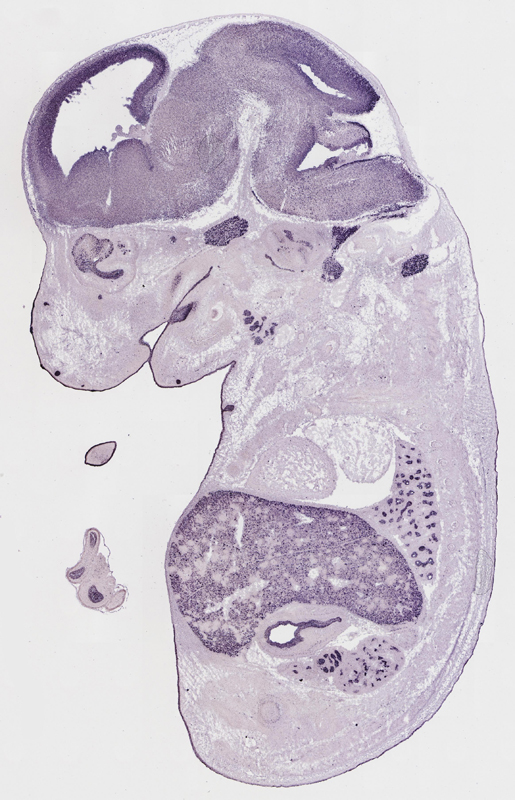

euxassay_003287_01:

embryonic day 14.5

euxassay_003287_02: